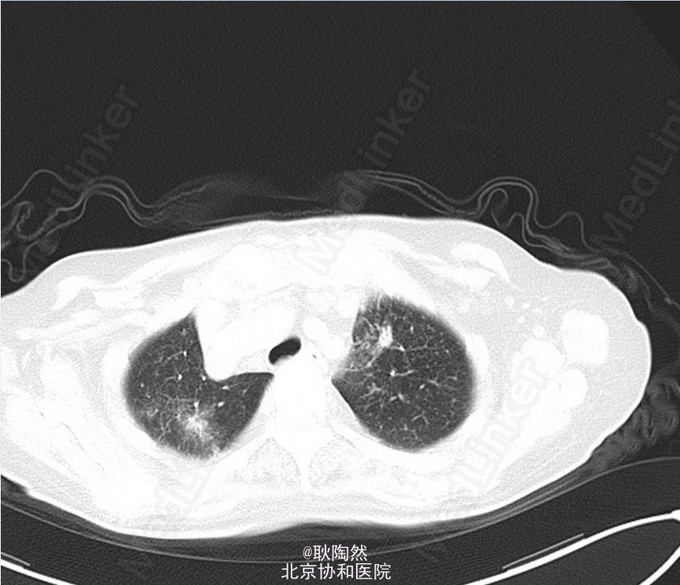

患者75岁老年女性,因“间断发热1年余,乏力、少语2周”于2014-12-25入院治疗。 2013年起患者无明显诱因出现发热,每日午后温度渐高,Tmax39℃,次日凌晨可降至正常。伴乏力,无盗汗、畏寒寒战、咳嗽咳痰等表现。外院胸部CT提示“肺部感染”,予莫西沙星治疗后体温正常。 2013-3患者出现T12椎体骨折,行手术治疗,术前有发热表现,予莫西沙星抗感染治疗后体温正常。2014-5因再次出现腰痛复诊,因前次手术窦道(左髂)迟迟未愈合,于左髂处取活检:坏死性肉芽肿,伴死骨形成,可见多核巨细胞及类上皮细胞,抗酸染色(-),不除外结核。 后患者间断发热。2014-8胸部CT示:右上肺尖后段、右中叶外侧段、左下肺外侧段散在片絮、云雾状不规则高密度灶,密度不均,提示感染;纵膈内未见肿大淋巴结。右肺病灶行肺穿活检:可见肺组织及部分横纹肌组织,肺组织变性坏死,周围小灶肉芽肿形成,纤维组织增生,慢性炎症细胞浸润,部分细胞增生。抗酸(-),PAS(-),六胺银(-)。 2014-12起患者出现神情淡漠,懒言少语,乏力加重,不能坐起或下床。遂入我科。 入我科后查PPD皮试:(+++);血T-SPOT.TB:MLC+IFN(A) 36SFC10^6MC,MLC+IFN(B) 704SFC10^6MC; 胸腹盆CT(平扫):右肺上叶后段胸膜下肿块大致同前;两上肺及右中肺粟粒样结节并两肺多发斑片索条及散在钙化灶,考虑结核性病变;两肺门多发钙化灶,纵隔多发淋巴结;双侧胸膜增厚,大致同前;胸8-腰4 椎体多发内固定器,部分椎体骨质破坏,可为椎体结核术后改变;胸11-腰3 椎体左旁多发低密度影并环形强化,考虑椎旁脓肿;骶骨前方、直肠后方片状低密度影,渗出性改变不除外。 行腰穿:脑脊液压力为88mmH2O。脑脊液常规:外观 无色透明,细胞总数 12*10^6/L,白细胞总数 0*10^6/L,单核 0,多核 0;脑脊液生化:CSF-Pro 0.76g/L,CSF-Cl 115mmol/L,CSF-Glu 1.5mmol/L。脑脊液抗酸染色(-)、脑脊液结核、非结核分枝杆菌DNA(-);脑脊液T-SPOT.TB:MLC+IFN(A) 24 SFC10^6MC,MLC+IFN(B) 132 SFC10^6MC;脑脊液细胞学:结论:淋巴细胞性炎症,WBC 1000/0.5ml,AL 阳性(+),AM 阴性(-),PC 阴性(-),TC 阴性(-),RBC -,CL ++,LY% 90%,MONO% 5%,NEUT% 5.000%; 考虑患者为播散性结核感染,有肺、骨、中枢神经系统受累。予异烟肼、利福喷丁、乙胺丁醇、拜复乐四联抗结核治疗。